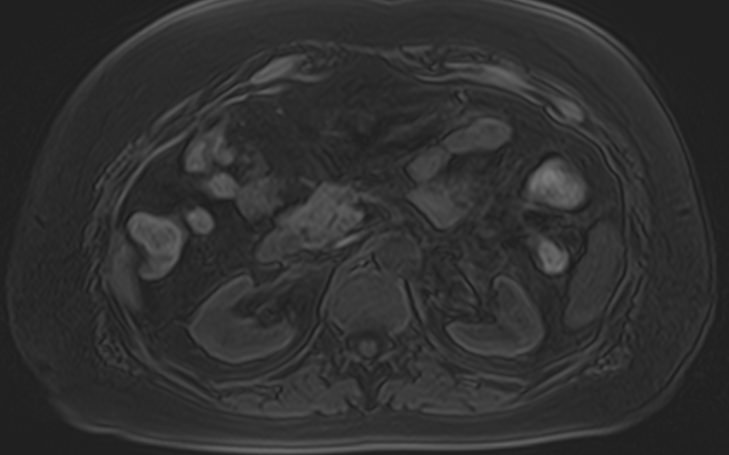

МРТ почек проводится для оценки состояния всех структур этого важнейшего органа выделительной системы, включая паренхиму, чашечки, лоханки почек и сосудистую систему. В клинике «Доступная медицина» исследование выполняется на томографе экспертного уровня TOSHIBA VANTAGE TITAN 1,5 Тесла, который обеспечивает изображения высокой четкости и контрастности, что позволяет проводить точную и достоверную диагностику заболеваний почек.

МРТ используется для диагностики злокачественных и доброкачественных опухолей почек. При этом большую ценность представляет МРТ почек с введением контрастного вещества. Процедура дает возможность не только выявить новообразования, но и установить степень развития патологического процесса, определить распространение метастазов на близлежащие органы. Только МРТ позволяет обнаружить псевдокапсулу новообразования. Такая информация крайне необходима, если речь идет об оперативном лечении рака почки с возможным сохранением органа. Также методика с высокой точностью определяет кистозные образования, распространение метастазов.

МРТ почек показывает:

Исследование используется при лечении различных воспалительных и дегенеративных процессов почек с целью анализа эффективности проведенной терапии. МРТ почек назначается пациентам при наличии противопоказаний к осуществлению рентгенограммы, урографии, в случае неэффективности КТ, ультразвукового сканирования. Дополнительно во время обследования диагност может выявить заболевания мочевыводящих путей, в частности, мочеточников. Показано проведение магнитно-резонансной томографии при эндокринных патологиях (при расстройстве функций надпочечников), злокачественном течении гипертонической болезни. С помощью МРТ почек удается установить травматические повреждения, подтвердить абсцесс органа, мочекаменную болезнь, врожденные аномалии строения.